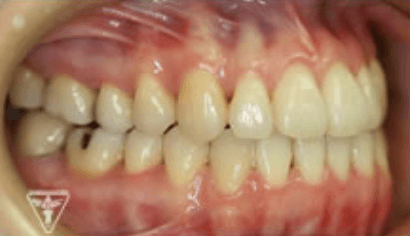

治療後

保定装置の装着

長期安定と後もどり防止のために、保定装置を装着します。

長谷川 信先生考案のフロッシュ装置(ゴムメタル使用)を夜間装置します。

治療前後の比較